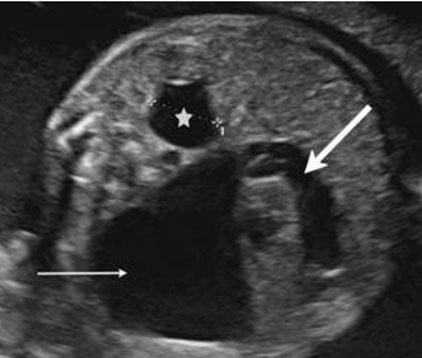

Previous work up few months ago was reviewed revealing an oval, circumscribed, heterogenous complex mass on the left breast, measuring around 10.7 × 6.8 × 6.8 cm at the left breast which is predominantly solid and with microcalcifications (Figure 2). Mammography was done revealing a large, irregular, complex mass occupying the entire left breast. An exophytic component through the lower inner quadrant was noted with diffuse skin thickening (Figure 3). Receiving hemoglobin of the patient is at 8 mg/dL which was subsequently managed with transfusion of blood products. The bleeding mass was also adequately controlled during the admission.

Figure 2: Ultrasound findings reveal a fungating wound, skin, and nipple thickening and retraction on the left breast. (A) Mass almost occupies the entire left breast and extends to the retroareolar region. (B) Oval, circumscribed, heterogenous, complex mass, predominantly solid with macrocalcifications ~10.7 × 6.8 × 8.6 cm. (C) Appears to extend to the pectoralis muscle.